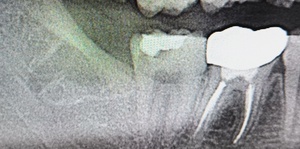

After(下親知らずの抜歯後) 横に生えた状態で埋まっている親知らずの抜歯後 虫歯がある親知らずの抜歯後 抜歯後の骨の状態のレントゲン像

親知らずを複数に分割してから、全て取り除きました。抜歯後は切った歯肉を元の位置に戻し、糸で縫って傷口を閉じます。

1年後、取り除いた親知らず周囲の骨がしっかり再生したことを確認しました。